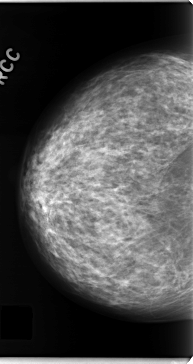

C_0130_1.RIGHT_CC

RIGHT_CC LINES 4720 PIXELS_PER_LINE 2504 BITS_PER_PIXEL 12 RESOLUTION 50 NON_OVERLAY